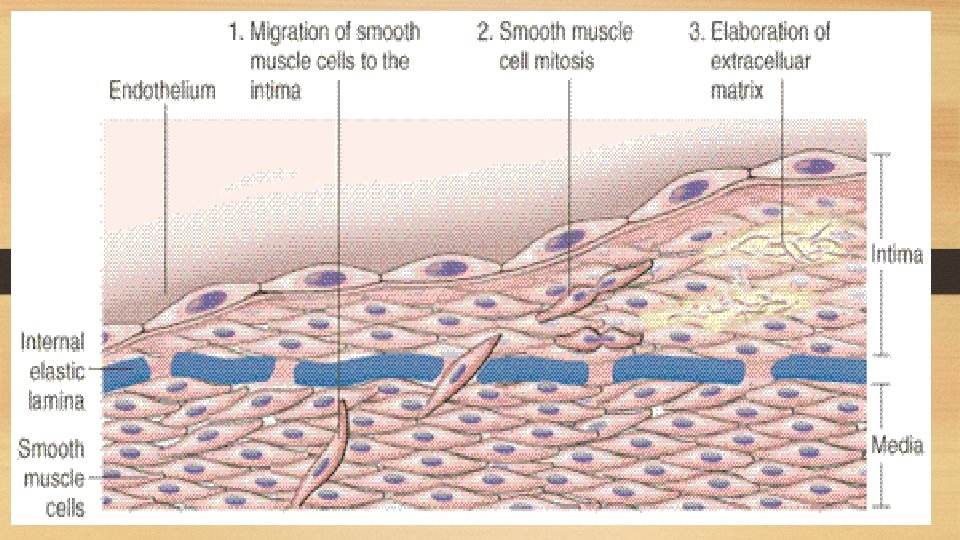

Pathogenesis of Atherosclerosis: i. Endothelial injury: - Is the initial triggering event in the development of lesions of atherosclerosis. - Risk factors such as hypertension, cigarette smoking and chronic hyperlipidemia can cause endothelial damage. ii. Role of blood monocytes: - Plasma LDL on entry into the injured intima undergoes oxidation. - The 'oxidized LDL' performs the following functions on monocytes and endothelium: a. For monocytes, oxidized LDL acts to attract, proliferate, immobilize and activate them to transform it to a lipid-laden foam cell after LDL engulfment. Death of foam cell by apoptosis releases lipid to form lipid core of plaque. b. For endothelium, oxidized LDL is cytotoxic. iii. Smooth muscle cell proliferation: - Endothelial injury causes adherence, aggregation and platelet release reaction at the site of exposed subendothelial connective tissue. - Migration of smooth muscles from media to intima occurs first, followed by Proliferation of smooth muscle cells which is stimulated by various mitogens, the most important of which is platelet-derived growth factor (PDGF).